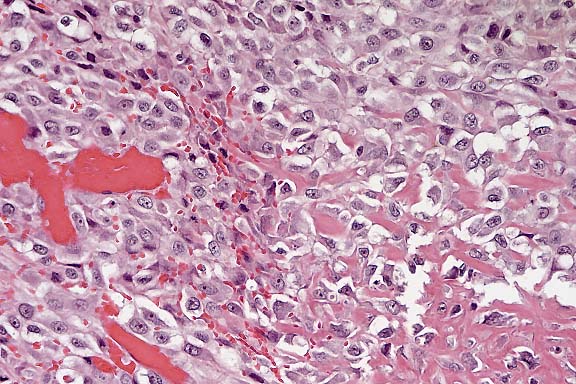

Case 25-2. Pericardium. Some clusters of the anaplastic sarcoma cells are producing a small amount of non-mineralized, hypereosinophilic, osteoid. 20X

Conference Note: The mass is composed of spindled and polygonal cells arranged in bundles, streams and whorls. Multifocally, neoplastic cells are separated or surrounded by a homogeneous eosinophilic matrix consistent with osteoid. Invasive growth, extensive necrosis, frequent mitoses and nuclear atypia indicate malignancy. By immunohistochemistry, many of the neoplastic cells are positive for S-100 protein. The essential feature of osteosarcoma, production of osteoid by malignant cells, is present. In humans and dogs, osteosarcomatous differentiation occurs rarely in malignant melanoma and malignant peripheral nerve sheath tumors. Thus, these neoplasms were considered in the differential diagnosis. Melanomas and nerve sheath tumors are often S-100 positive; S-100 positivity has also been reported in human osteosarcoma. We are unaware of any reports of osteosarcomatous differentiation in feline melanomas or nerve sheath tumors. No histologic features highly characteristic of melanoma (such as brown to black cytoplasmic pigment) or nerve tumor (such as Verocay bodies) were observed in the examined sections. Thus, the evidence supports the contributor's diagnosis of osteosarcoma. Whole body radiographic examination is helpful in excluding the possibility of an undetected primary osteosarcoma in bone when extraskeletal osteosarcoma is suspected.